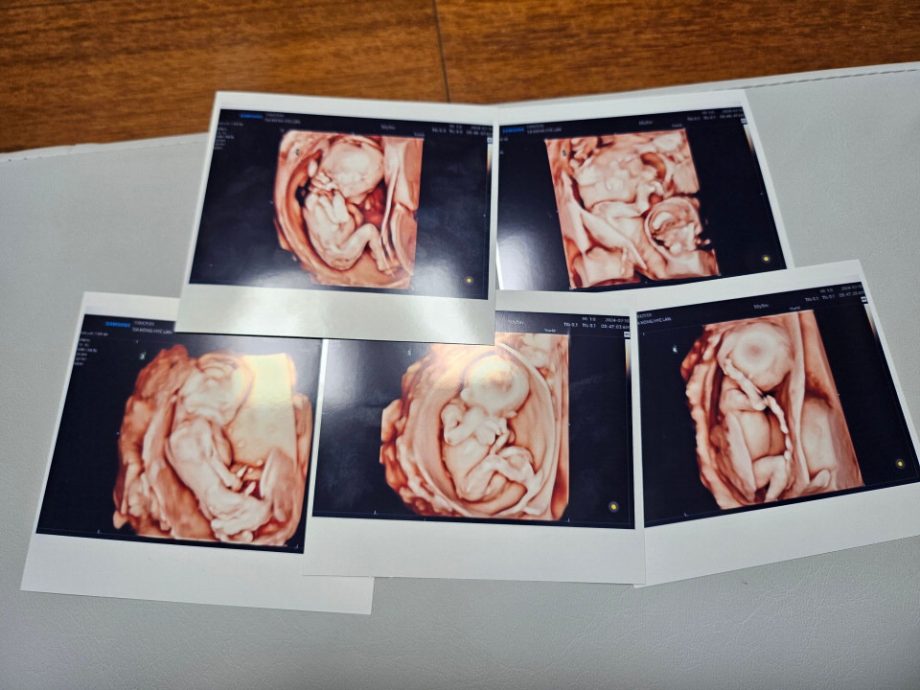

韩国首例 自然受孕五胞胎平安诞生

(首尔21日中新电)韩国加图立大学附属首尔圣母医院20日消息称,居住在韩国京畿道东豆川市的一对夫妻当天喜获五胞胎,性别三男二女。这是韩国首次平安诞生自然受孕的五胞胎。

据韩联社报道,这对夫妇年纪在30出头,于去年10月结婚。男方在一所高中任教,女方为教育公务员。女方产检时发现患有多囊卵巢综合征,在接受首次排卵治疗后自然受孕。产妇预产期虽在12月,但腹部早已达到临盆状态,加上其患有先兆子痫,无法推迟生产,故在第27周接受了剖腹产手术。